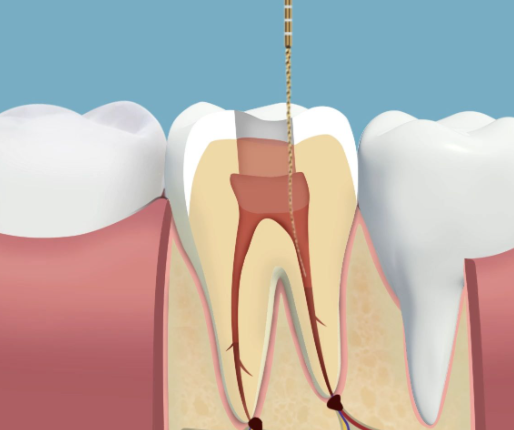

微笑青澄口腔门诊部 根管治疗:800元起/颗